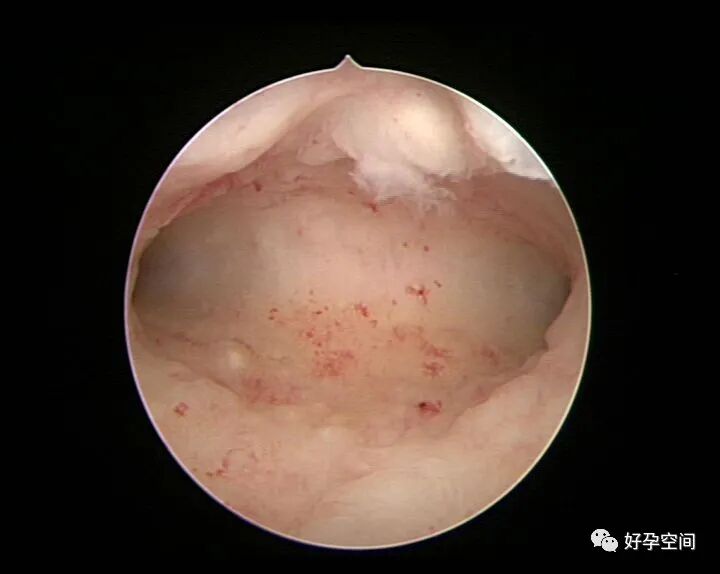

病例06:密布结节性肉芽肿内膜发红